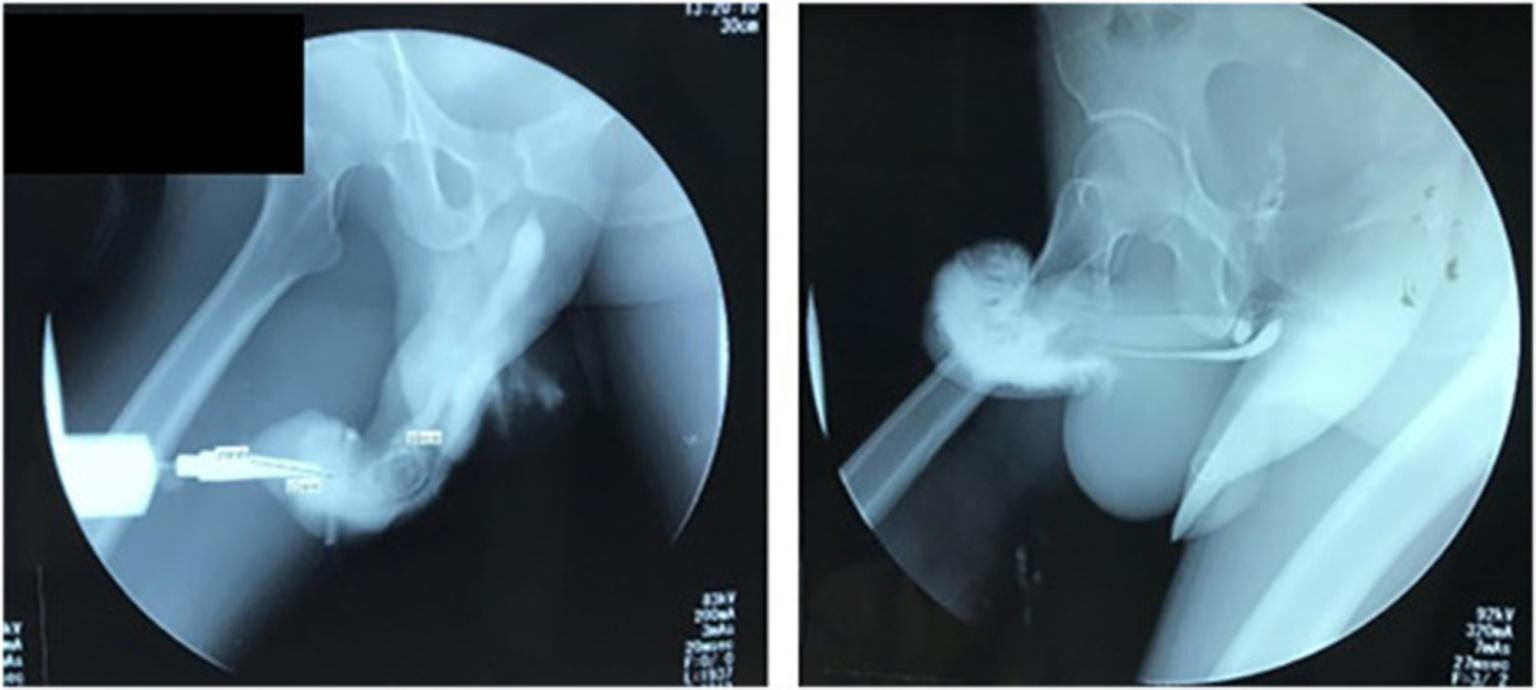

Мужчине из Индонезии пришлось перенести экстренную операцию после того, как он сломал пенис из-за рискованной позы во время секса. Исследование случившегося опубликовали в журнале Urology Case Reports. Несчастный случай произошел, когда неназванный 37-летний мужчина решил попробовать со своей возлюбленной положение «обратной наездницы» (“reverse cowgirl”): женщина находилась сверху и спиной к своему мужчине.

- По словам хирурга из Великобритании, доктора Карана Раджа, «обратная наездница» - «самая опасная» поза в сексе, на которую приходится колоссальные 50% переломов.